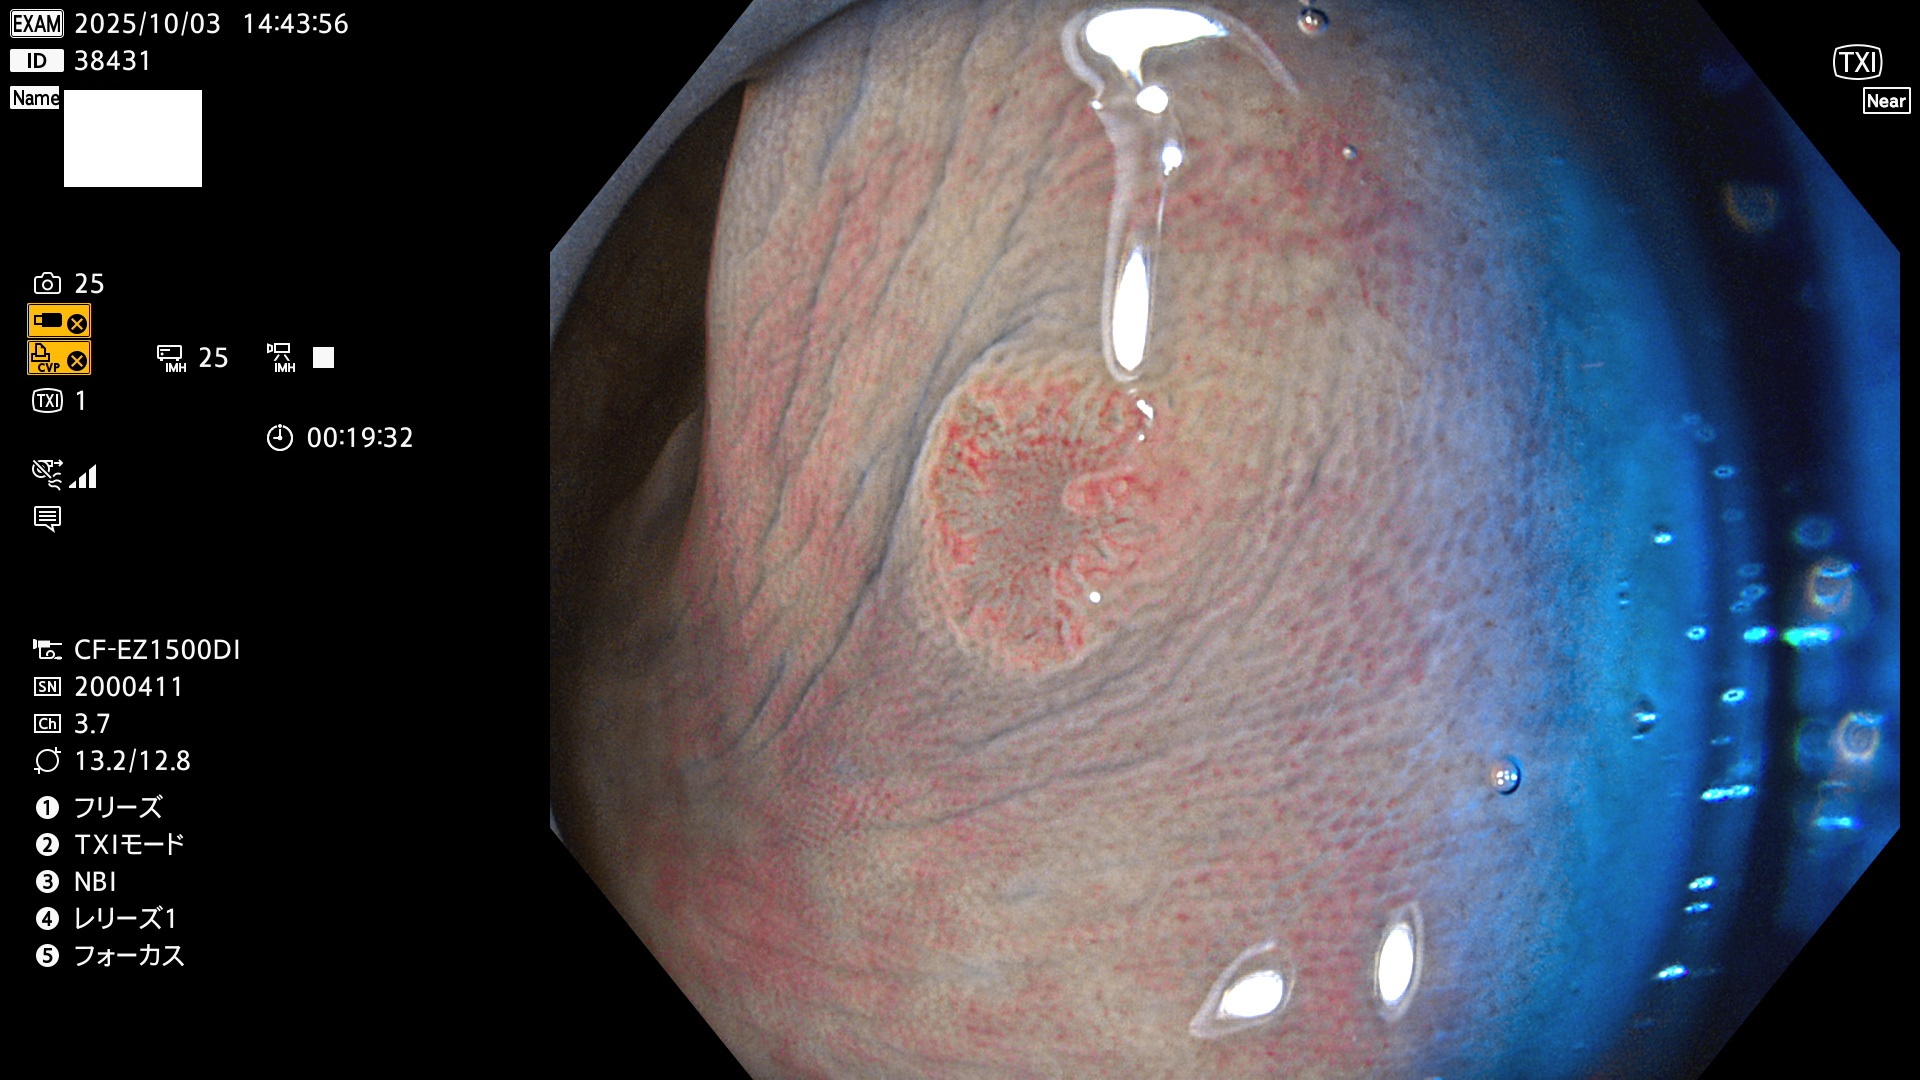

完全に平坦な物をUb、陥凹している物をUcと呼びます。Ubは認識が困難で、Ucはびらん(炎症)と紛らわしいために見落とされやすく、「内視鏡後・大腸癌」の原因になります。

専門的)何故、陥凹していると危険? 癌遺伝子の変異が蓄積すると細胞分裂が盛んになり隆起するのでは?と通常は思われるでしょう。しかし実際は逆です。これは2022年の記事にある「細胞はストレスに直面したら細胞分裂を止める(Dormancy 細胞老化に入り休眠する)という生命の基本的現象」によるものです(Oncogene Stress)。細胞老化を起こすのが癌抑制遺伝子で、この安全装置(ブレーキ)が壊れると癌になります(休眠からの覚醒)。ですから陥凹は「まだ癌では無いが癌化の直前」を意味します。特に「小サイズなのに陥凹している」病変は短期間に腫瘍進化(IntraTumor Heterogenity⇒2021年記事)が起きたことを意味します(=ゲノム不安定性)。

専門的)Uc=De Novo癌? 内視鏡の解像度が低かった時代、このような説もありました。しかし今日の高精度内視鏡では良性の微小なUc型腺腫(APC遺伝子異常の腺腫)が日常的に見つかります。Ucこそが多段階発癌(Adenoma-Carcinoma Sequence)のMain Routeです。

毎週の検査(木・金・土・日)に発見されたUbとUc型・腺腫を、その週の日曜の夜にUPし1週間、提示します。

2025年10月2日〜10月5日の4日間(40件)9個 (Uc_ADR=9個/40人=23%)